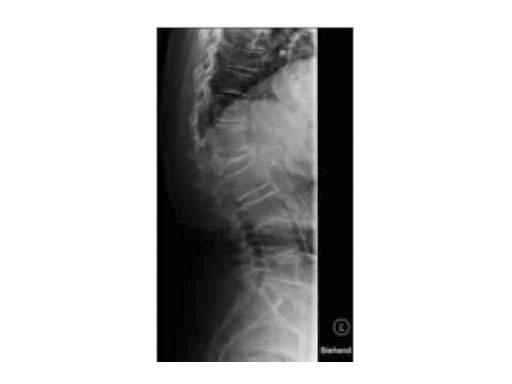

A 78-year-old woman was affected by steroid induced osteoporosis. She had persisting pain (mechanic and muscular) due to static imbalance (hyperkyphosis) and nonunion 8 months after a minor trauma with a vertebral compression fracture and vertebra plana of L1, and development of symptomatic stenosis of the spinal canal with loss of mobility over time. Pre-existing degenerative lumbar scoliosis was increased by the fracture.